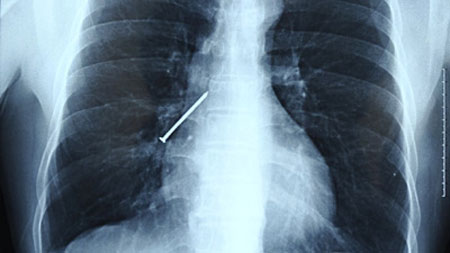

Sau 3 lần vất vả gắp chiếc đinh dài 15cm ra khỏi cơ thể của một người thợ mộc, các bác sĩ ở Trung Quốc cuối cùng mới thành công.

Khi đang ngậm đinh ở răng để làm việc, Li Xiangyang (48 tuổi) ở thành phố Hoàng Thạch, tỉnh Hồ Bắc bất ngờ ho và nuốt nó vào người. Ông nhanh chóng được đưa tới một bệnh viện gần trường Đại học Vũ Hán để cấp cứu. Tại đây, qua chụp X-quang, các bác sĩ phát hiện chiếc đinh nằm ở phổi phải.

Chiếc đinh dài 15cm nằm trong phổi của Li.

Nhận thấy cần phải lấy nó ngay ra khỏi cơ thể, giáo sư Hu Ke luồn một ống soi phế quản xuống cổ họng để lấy chiếc đinh ra. Tuy nhiên, khi ông Hu sắp lấy được chiếc đinh ra khỏi miệng, thì Li lại ho và khiến chiếc đinh rơi xuống cổ họng.

Lần này, chiếc đinh lại nằm ở phổi trái và giáo sư Hu lại tiếp tục lấy nó ra. Nhưng cũng như lần trước, Li vô tình nuốt chiếc đinh và nó lại biến mất khi sắp được lấy ra.

Loay hoay mãi mà không tìm thấy chiếc đinh nằm ở phổi, các bác sĩ sau đó phát hiện nó đã trôi xuống dạ dày của bệnh nhân. Cuối cùng, bác sĩ dùng ống soi dạ dày để lấy được nó ra khỏi bụng của ông Li.